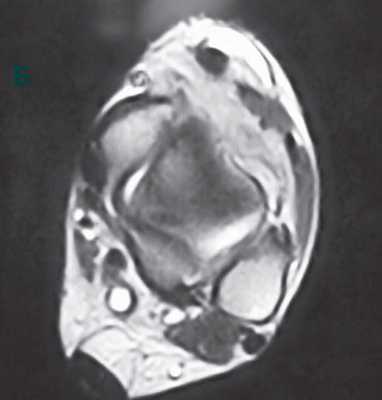

У данного пациента имеет место дисфункция сухожилия задней большеберцовой мышцы с развитием плоскостопия. Передний отдел стопы направлен наружу. Симптом «слишком много пальцев». При осмотре стопы сзади мы 3,4,5 палец стопы.

- Признак «слишком много пальцев». Если смотреть на стопу со стороны спины пациента, обычно мы видим только пятый и половину четвертого пальца стопы. При плоскостопии мы увидим большее число пальцев.